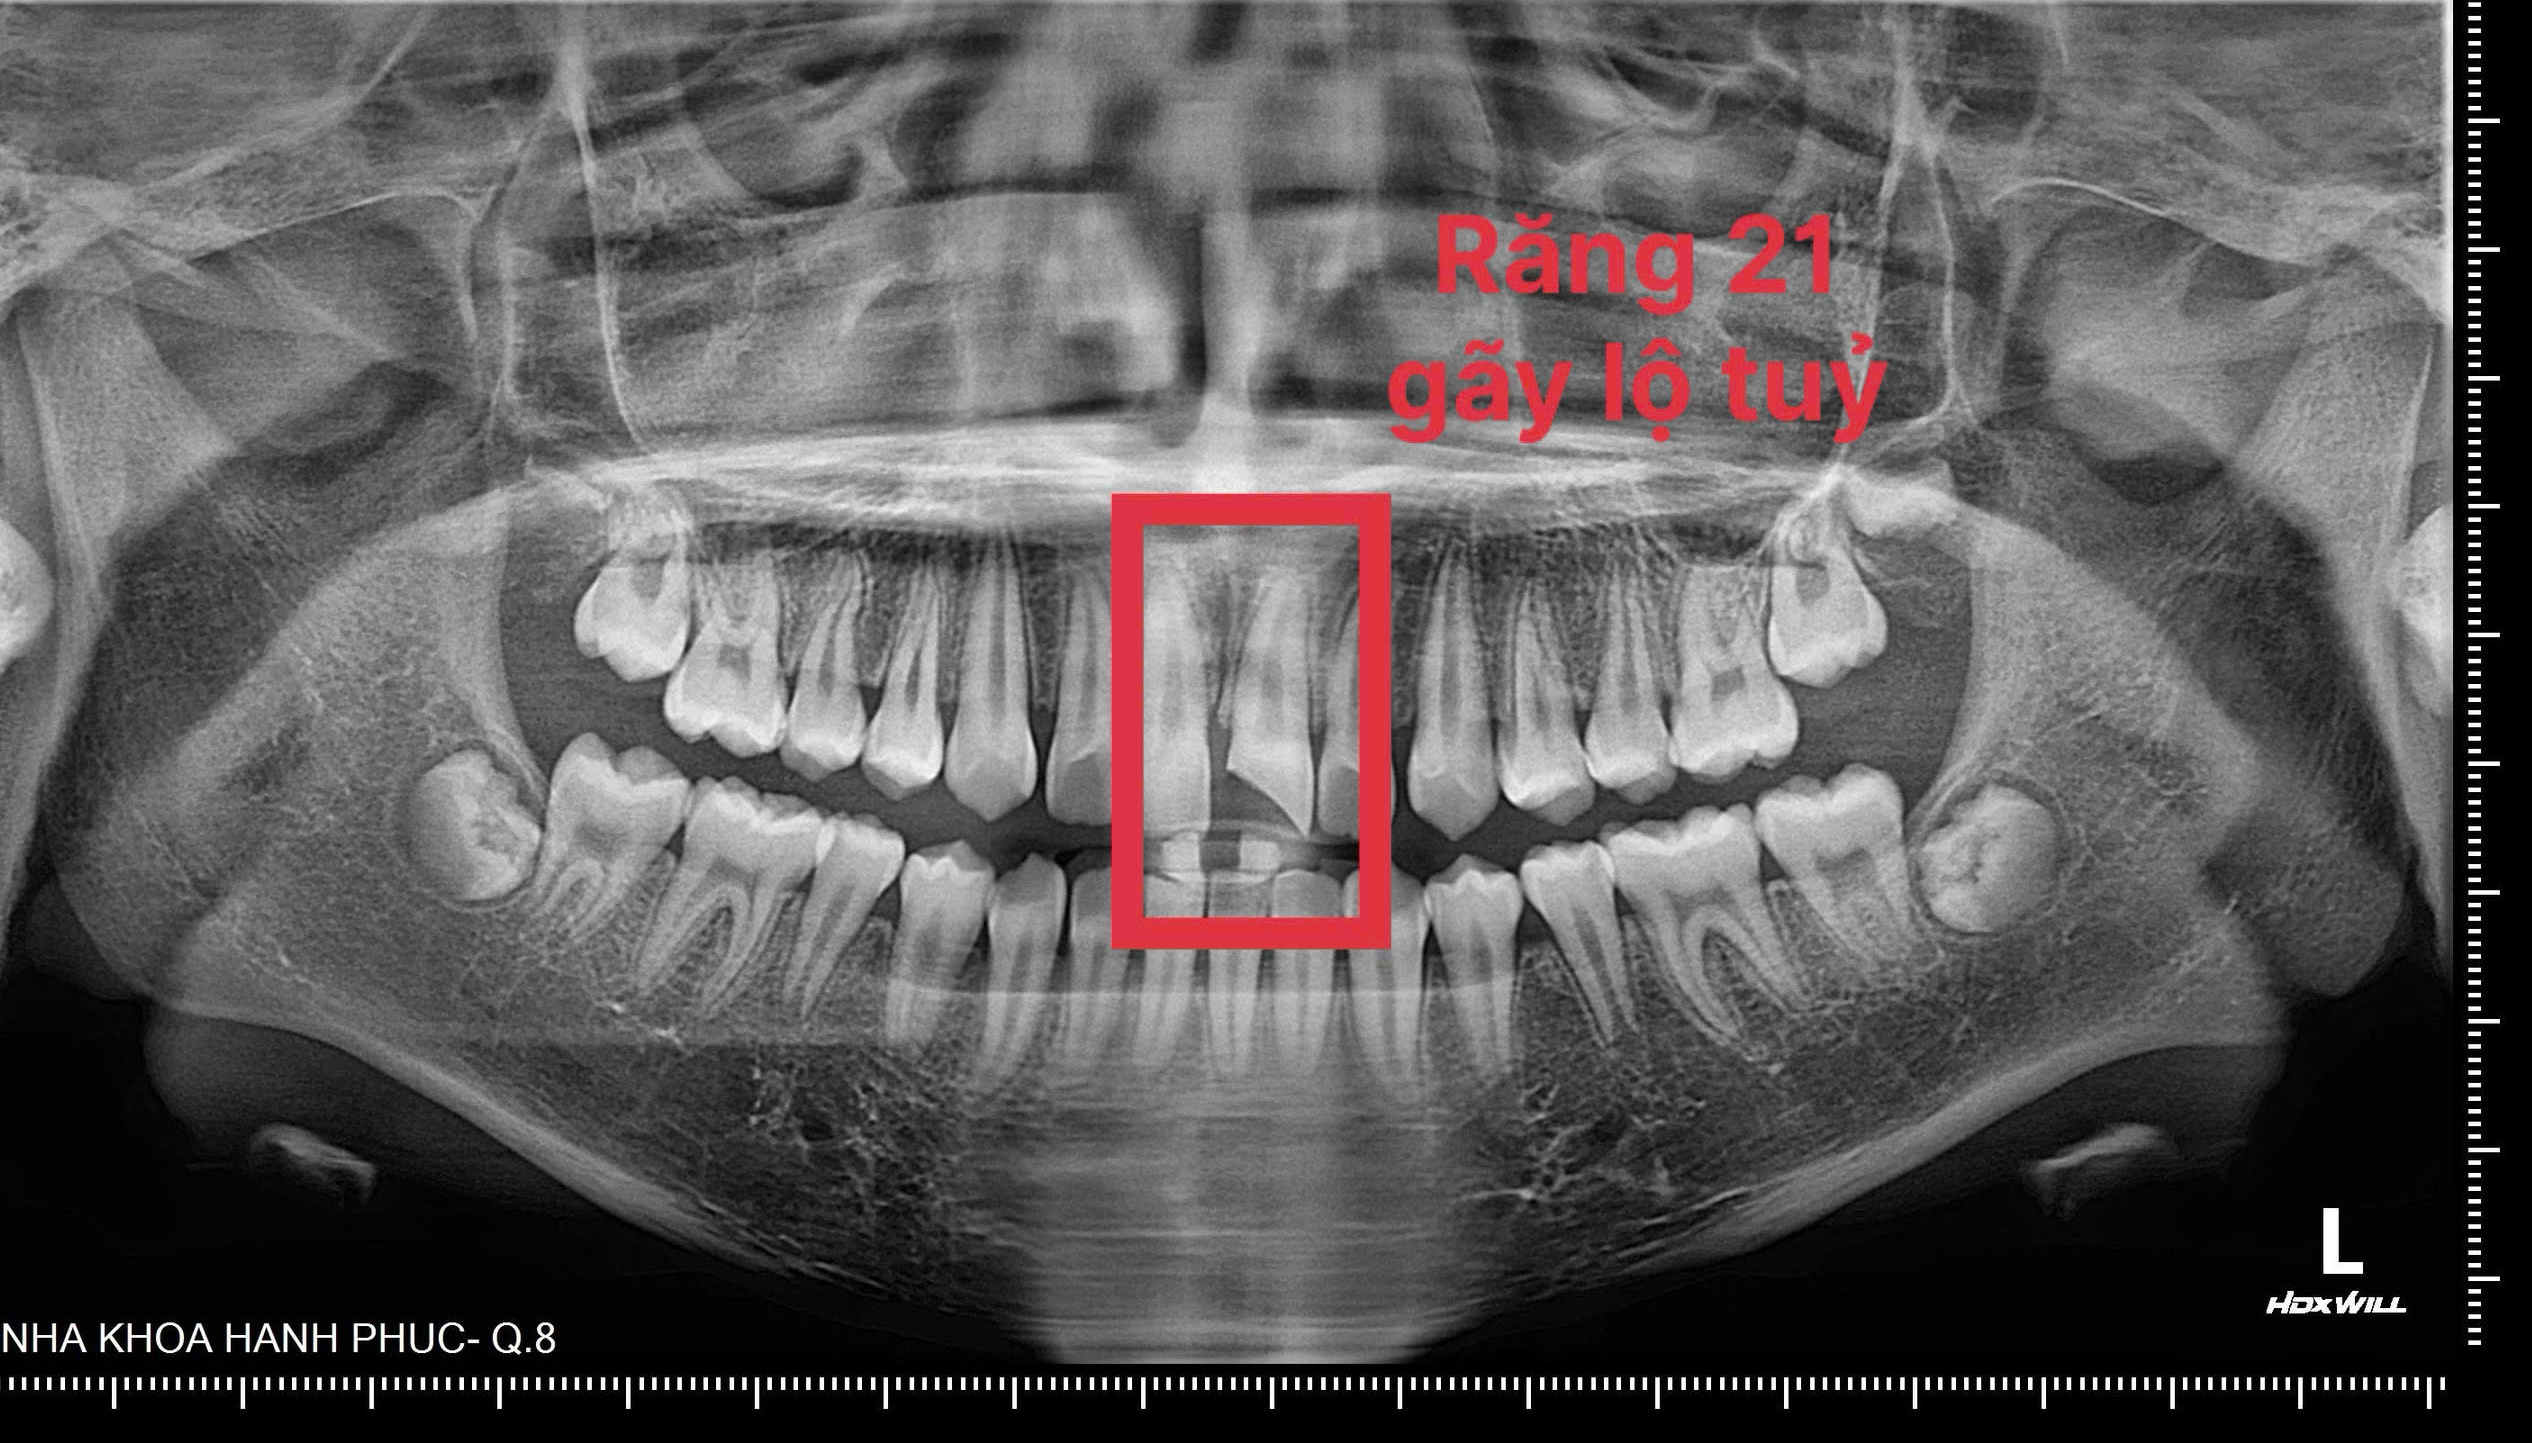

Một bé trai 10 tuổi được đưa đến Nha khoa Hạnh Phúc trong tình trạng mẻ răng cửa kèm ê buốt khi ăn uống nóng, lạnh. Qua thăm khám lâm sàng và chụp phim kiểm tra, bác sĩ ghi nhận tổn thương răng sát tủy, có nguy cơ ảnh hưởng đến sức sống của răng, và đã chỉ định phương pháp điều trị phù hợp để bảo tồn răng thật cho bệnh nhi.

Qua thăm khám lâm sàng và chụp phim kiểm tra, bác sĩ ghi nhận vùng răng mẻ sát tủy, có tình trạng lộ tủy răng. Trước nguy cơ ảnh hưởng đến sức sống của răng, bác sĩ chỉ định che tủy trực tiếp bằng vật liệu sinh học Biodentine nhằm bảo tồn răng thật. Quá trình điều trị diễn ra trong khoảng 45 phút, bệnh nhân đáp ứng tốt, sau đó được trám tạm tái tạo thẩm mỹ vùng răng tổn thương và hẹn tái khám theo các mốc 1 tháng, 3 tháng và 6 tháng để theo dõi.